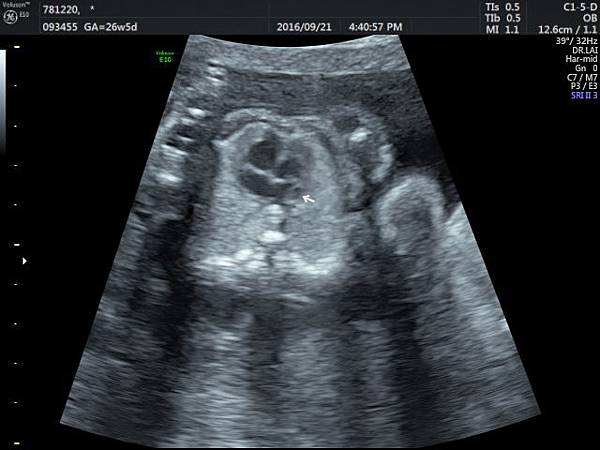

2016年9月21日幫一位懷孕26歲懷雙胞胎的孕婦看胎兒心臟超音波,孕婦目前26週,雙胞胎大小相差四週,高層次超音波除了小的胎兒臍動脈血流有問題之外,沒有其他異常發現,經過我的檢查,我的診斷是小的胎兒有持續性左側上腔靜脈(附圖1~5)。

正常情況左側的上腔靜脈在胚胎發育過程應該要退化,左側頭頸部的靜脈回流是流向右側的上腔靜脈再回到右心房,而持續性左側上腔靜脈是這條血管沒有退化繼續存在,它的血流一般會流入左心房背部的冠狀竇(coronary sinus)再經由冠狀竇回到右心房,因為最終都是回到右心房,理論上沒有什麼問題,只是為何它會不退化呢?是否有什麼因素造成它不退化這才是重點所在,所以做染色體基因檢查的理由就是找出是否有原因。

因為冠狀竇變大,超音波影像常被誤解為心房中隔缺損,兩者的預後差很多,鑑別診斷需要經驗,我常跟孕婦說,如果只給我10分鐘檢查一位胎兒,我會選擇看胎兒心臟,因為心臟就像一部車子的引擎,胎兒先天性心臟病常會合併染色體基因的問題,藉由心臟檢查,可以縮小範圍。

持續性左側上腔靜脈如果沒有合併其他異常,可以視為正常的變異,不需要任何治療,也不會有什麼特別問題,但是如何排除是否合併其他問題呢?我建議需要做染色體及基因晶片檢查,並且需要做高層次超音波排除其他器官是否異常。